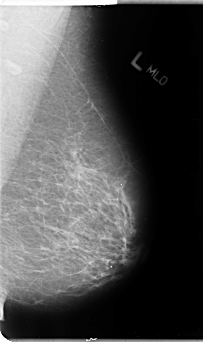

B_3106_1.LEFT_MLO

LEFT_MLO LINES 4784 PIXELS_PER_LINE 2832 BITS_PER_PIXEL 12 RESOLUTION 50 NON_OVERLAY